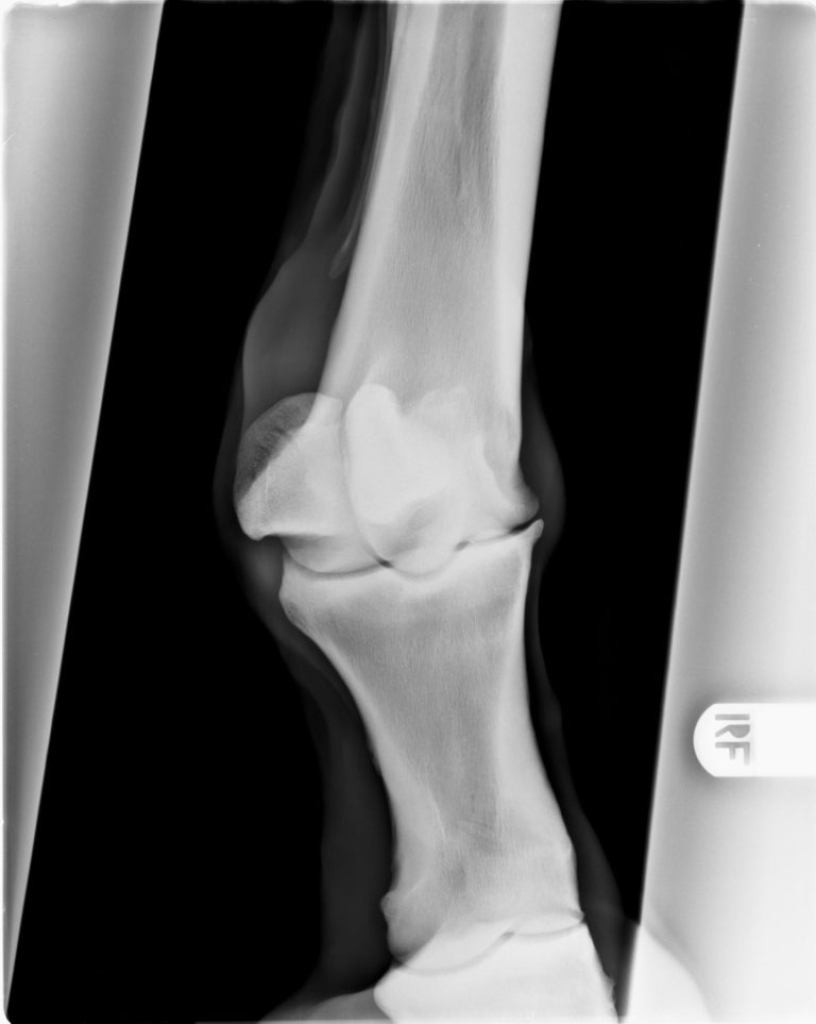

Röntgenopname van een gewricht met artrose

Door een kleine beschadiging kan uiteindelijk soort vicieuze cirkel ontstaan waarbij de kwaliteit van het kraakbeen langzaam aan steeds slechter wordt. Als gevolg van de schade aan het kraakbeen gaat ook het onderliggende bot reageren, het gaat aan de randen van het gewricht nieuw bot vormen. Dit is op een röntgenfoto goed zichtbaar als scherpe randjes of bot nieuwvormingen rond het gewricht. Het kraakbeen zelf is helaas niet in beeld te brengen met röntgenfoto’s, daarom is op een röntgenfoto in een heel vroeg stadium van artrose nog niks zichtbaar.

De diagnose van artrose is te stellen op basis van röntgenfoto’s. Op de röntgenfoto’s zien we bij artrose vaak veranderingen aan de randen van de gewrichten. Meestal ontstaan er scherpe randen rond het gewricht.